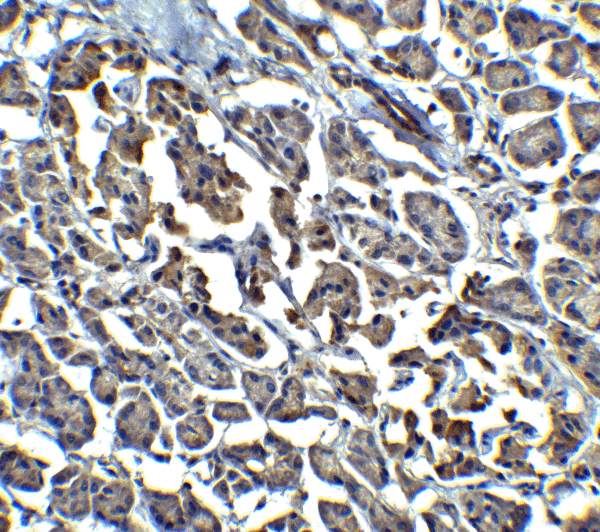

IHC (Immunohistochemistry)

(Immunohistochemistry of EndoG in human pancreas with EndoG antibody at 15 μg/mL.)